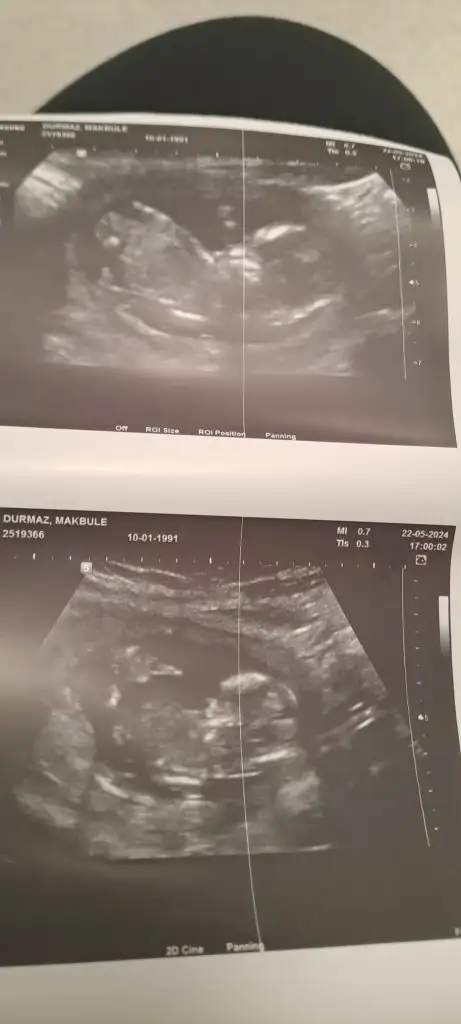

Banada bakarmsnDaha net bir goruntusu olsaydi nubuna bakarak yorum yapabilirdim ama biraz bulanik net degil foto.hayirlisi olsun saglikli olsun

Daha net bir goruntusu olsaydi nubuna bakarak yorum yapabilirdim ama biraz bulanik net degil foto.hayirlisi olsun saglikli olsun

Bakarmsn banadaDaha net yokmu sanki foto bulanik cozemedim.birsey soylemekde istemiyorum yaniltici olabilir nubu gorunuyor ama net degil

EderimEki Görüntüle 1993062 Bebegimin 11.4 gunluk ultrason görüntüsüne göre bilen varsa tahmin edebilirmisnz. Yarin da doktora gidecegim ama genelde bu sekilde duruyor. Sakliyor.

Kızlar ikinci resim de 12.4 gunluk renkli ultrason. Videodan aldim. Cok net degil. Bir saniyeligine açıyor sanki

Eki Görüntüle 1993662 bu da normal ultrason 12.4